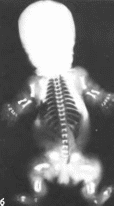

Рис.

63.

Танатофорная карликовость,

а

мнкромелия, коническая форма пальцев

рук, макроцефалия, запавшая пере-

носица.

многочисленные кожные складки: б

рентгенограмма новорожденного

вертикальный

диаметр гсл позвонков уменьшен, в

ннжнегрудиом и поясничном

отделах

позвоночника межпозвоночные пространства

увеличены, грудная клетка

узкая,

ребра и длинные трубчатые кости

укорочены.